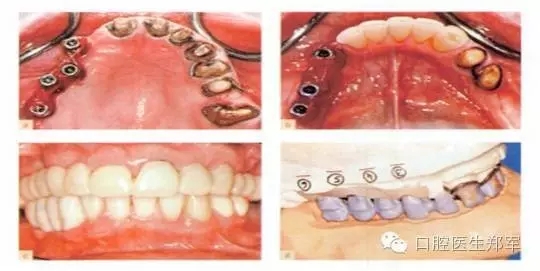

圖11 a和b 種植體基臺和基牙的預備。c 再次評估暫時修復體并確認其功能、美學和穩(wěn)定性。d 根據(jù)回切硅膠導板和暫時修復體交叉上牙合架技術修整最終修復體蠟型。 |

圖12 a和b最終修復體(圖由修復學專家Dr 0 Gelfan, Professor Z Artzi , and Mr B lndig.提供) |